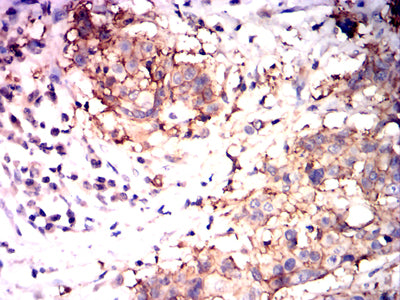

Immunohistochemical analysis of paraffin-embedded human esophageal cancer tissues using IL22 mouse mAb with DAB staining.

Immunohistochemical analysis of paraffin-embedded human ovarian cancer tissues using IL22 mouse mAb with DAB staining.